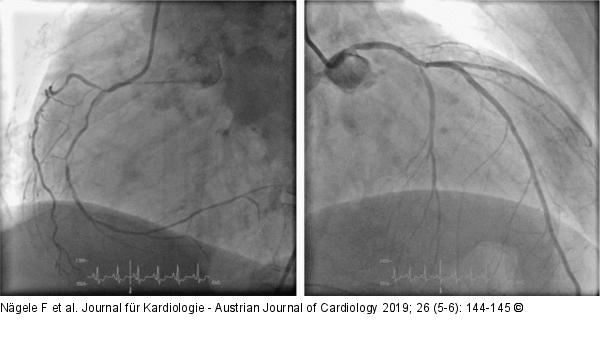

Abbildung 1: Dreigefäß-KHK Dreigefäß-KHK in der CAG als Ursache der ischämischen Kardiomyopathie. |

Abbildung 1: Dreigefäß-KHK

Dreigefäß-KHK in der CAG als Ursache der ischämischen Kardiomyopathie. |